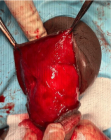

Penile fracture is a rare urological emergency typically characterized by an audible “cracking” sound, immediate detumescence, and rapid penile swelling following trauma to an erect penis. We present clinical and intra-operative images of a 37-year-old man with a proximal tunica albuginea tear confirmed at urgent exploration and repaired with absorbable sutures. Early surgical exploration with hematoma evacuation and primary repair remains the preferred approach to reduce long-term complications such as penile curvature and erectile dysfunction.

Figure 1